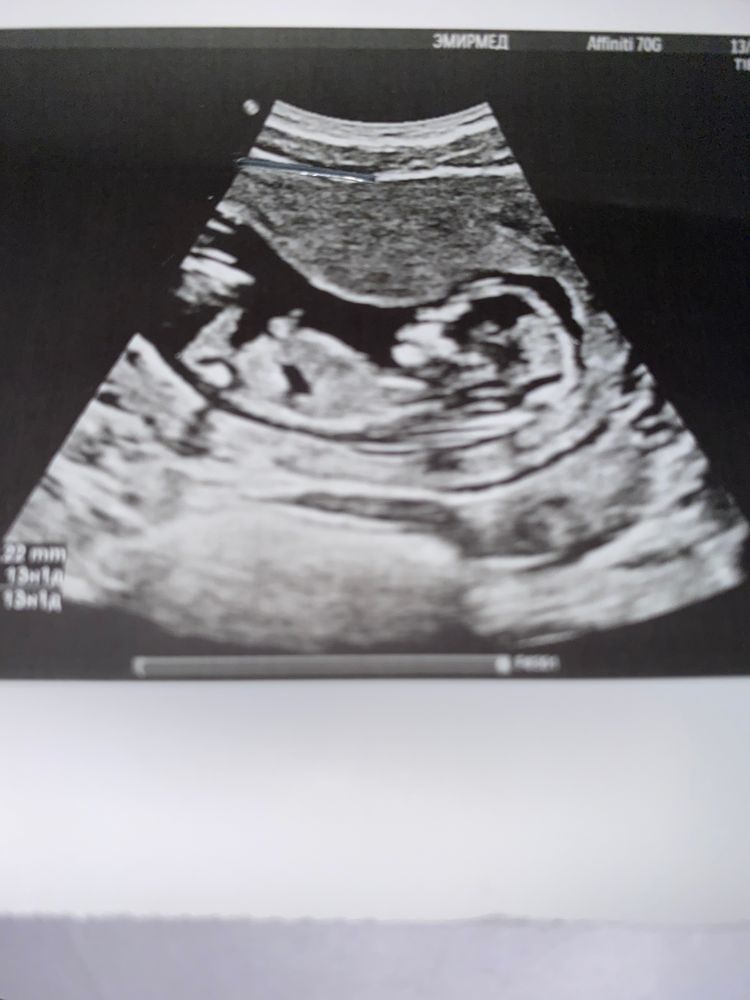

Софа в Клуб беременных год Девочки,по узи можете определить пол. Пол малыша 13 недель 1 день я сама думаю девочка Посмотрите еще 20 записей на эту тему Отменить Ответить Мама Даша Вам не сказали пол? Мне на 11 недели сказали, пол так и не поменялся если что. А так говорят, что с этой стороны девочка лежит, а мальчики как раз с другой 14.09.2024 Ответить Анастасия Ракурс немного не тот, тут ребёнок сбоку, так пол не определить. 13.09.2024 Ответить Помогите определить пол) Определить пол ребенка Чаты Беременных Выберите чат: Январята-2026 Февралята-2026 Мартята-2026 Апрелята-2026 Майчата-2026 Июнята-2026 Июлята-2026 Августята-2026